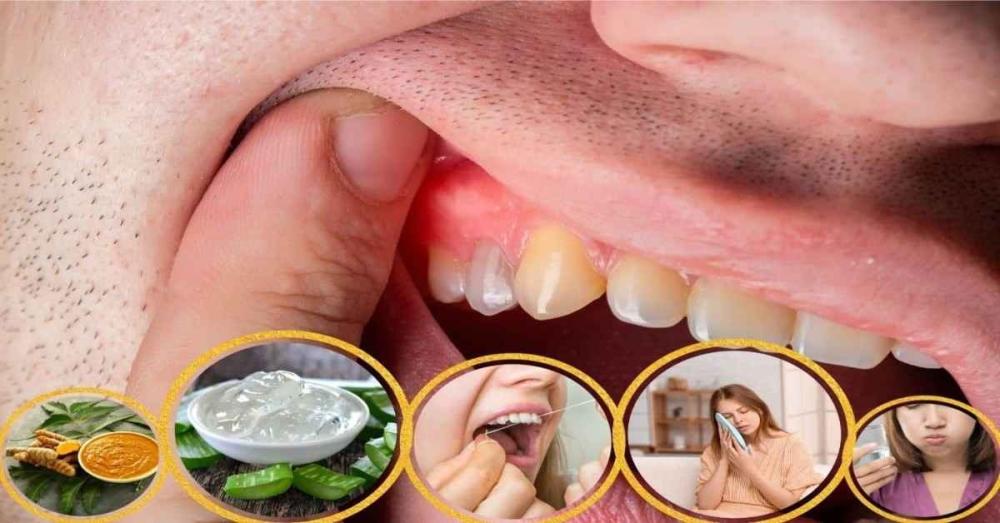

حين تضطرب اللثة، يختل توازن الفم بأكمله، فهذه الأنسجة الوردية الرقيقة ليست مجرد إطار جمالي للأسنان، بل هي درع بيولوجي يحمي الجذور ويثبتها في عظام الفك ويحافظ على استقرار الابتسامة. يبدأ الالتهاب غالبًا بإشارات خفيفة؛ نزيف بسيط، تورم طفيف، أو إحساس بحرقة عند المضغ. إشارات صغيرة. لكنها ذات دلالة.

التهاب اللثة هو استجابة التهابية تصيب الأنسجة المحيطة بالأسنان نتيجة تراكم البلاك البكتيري عند حافة اللثة، حيث تتجمع بقايا الطعام وتتحول إلى بيئة خصبة لنشاط الجراثيم إذا لم تتم إزالتها بانتظام. تشمل أبرز مظاهره:

- احمرار ملحوظ يغيّر اللون الطبيعي للثة

- تورم يجعل النسيج يبدو أكثر انتفاخًا ولمعانًا

- نزيف عند تنظيف الأسنان أو استخدام الخيط

- رائحة فم غير مستحبة

- حساسية أو ألم خفيف عند المضغ

في هذه المرحلة يكون التدخل المبكر ضروريًا، ويُعد علاج مشاكل اللثة طبيعيا خيارًا داعمًا يساعد في تقليل الالتهاب وتحسين حالة الأنسجة قبل تطورها إلى مراحل أعمق.

التهاب اللثة لا يظهر فجأة، بل يرسل إشارات واضحة. من العلامات الدالة:

- نزيف عند تفريش الأسنان

- تغير لون اللثة إلى الأحمر الداكن

- تورم وانتفاخ غير طبيعي

- رائحة فم مستمرة

- حساسية أو ألم عند المضغ

التهاب اللثة يمر بمراحل متعددة يمكن تمييزها بصريًا. تشمل المظاهر الشائعة:

- احمرار بسيط عند الحافة

- تضخم واضح يجعل اللثة تبدو منتفخة

- انحسار اللثة في المراحل المتقدمة

- نزيف عند اللمس الخفيف

معرفة هذه الأنواع تساعد في بدء علاج مشاكل اللثة طبيعيا في الوقت المناسب قبل تفاقم الحالة.